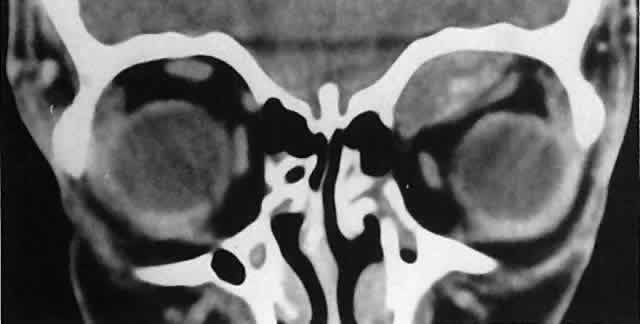

Acute blood cyst formation in this age group makes the distinction between a pre-existent but clinically silent lymphangioma and a rapidly emerging rhabdomyosarcoma a common orbital diagnostic problem. Evidence suggesting an orbitallymphangioma includes the variable finding of conjunctival or eyelid components of the malformation.86 Conjunctival lesions appear as ectatic channels filled with clear or hemorrhagic fluid. Eyelid ecchymosis may result from the seepage of blood out of the thin-walled orbital cysts. Additional developmental anomalies of the eye and adnexa may be present. Other head and neck involvement may be manifest as local hypertrophy (e.g., of the cheek or lips), and cystic palatal lesions may be seen. CT discloses a single or multilobulated mass, which represents only the blood cyst portion of the tumor (Fig. 14). Individual lobules may have different radiodensities depending on the presence of clots or liquefied blood within each cyst (Fig. 15). A generalized increase in orbital dimensions suggests a long-standing, probably congenital process. Echography may help differentiate the cystic components of lymphangioma from cellular rhabdomyosarcoma. Echography shows the blood cysts to be acoustically inactive spaces, with extremely low internal reflectivity (Fig. 16). Clots within the cysts can increase internal heterogeneity, however. MRI has virtually eliminated the need for diagnostic biopsy in this condition, because of its ability to show differing magnetic properties of suspended, degrading blood products (Fig. 17).

The intimate association of orbital lymphangiomas with structures critical to normal vision makes their complete excision almost impossible without incurring vision loss. Because their vascular components do not actively proliferate, the response to radiation therapy is limited and probably is proportionate to whatever lymphoid tissue is present. The presence of a blood cyst is not in itself an indication for treatment if vision is not impaired. In many cases, the blood resorbs during several weeks without residual problems. Frequently, however, vision is compromised by the sudden expansion of multilobulated cysts that surround the optic nerve, and simple observation may result in permanent deficits. Treatment requires evacuation of the offending cysts in a conservative manner consistent with preservation of vision.84 Because the channels of a lymphangioma are hemodynamically isolated from the systemic circulation (“no flow anomalies”),63 their surgical decompression does not produce brisk new bleeding from within them. Rather, the hemorrhagic risk of surgery involves intraoperative and, more often, postoperative, intrinsic bleeding, creating new blood-filled macrocysts.62 Conservative surgery restricts intraorbital manipulation, involves evacuation of offending blood cysts, and avoids disturbance of nonexpanded portions of the lymphangioma. Extensive dissection for cosmetic purposes should be undertaken with the same respect for the fragility of nonexpanded channels. TRAUMATIC ORBITAL HEMATOMA Although the diagnosis of a traumatic orbital hematoma would seem obvious on the basis of history alone, some element of trauma within a few days of the onset of proptosis is such a common historical finding among small children that it may have little differential value. Conversely, a history of culpable trauma may not always be forthcoming, as in cases of child abuse. In penetrating orbital injuries, the entry wounds suggest the diagnosis. Retained foreign bodies should be ruled out. In blunt injuries, other diagnostic clues are helpful. Ecchymosis may be present but also may be a feature of granulocytic sarcoma, neuroblastoma, or lymphangioma with recent bleeding. CT may show an associated fracture. Most orbital hematomas that result from blunt injury occur in the potential subperiosteal space (Fig. 18). The lack of adjacent sinus opacification and the absence of systemic toxicity differentiate this entity from a subperiosteal abscess, which can have a similar appearance.59 Echography shows the low acoustic reflectivity characteristic of fluid-filled spaces. If a traumatic orbital hematoma has compromised vision by acutely elevating orbital pressure, the pressure should be reduced promptly with a lateral canthotomy and cantholysis. If, conversely, vision is compromised because of extreme globe displacement and optic nerve attenuation, the hematoma should be evacuated.87 This is a relatively simple procedure if the blood is compartmentalized in the subperiosteal space. We favor a lid crease incision, with dissection between orbicularis muscle and orbital septum to the orbital rim. The subperiosteal space is then entered, and the hematoma is evacuated. If vision is not compromised, patients can be treated conservatively. Spontaneous absorption generally follows, but hematomas occasionally enlarge with osmotic imbibition. DERMOID CYST Dermoid and epidermoid cysts often occur in the orbit and paraorbital region. Epidermoid cysts are lined by stratified squamous epithelium and are filled with desquamated keratin. The walls of dermoid cysts include dermal appendages that contribute sebum, sweat, and hair shafts to the cyst contents. Both forms probably result from abnormal invagination of surface ectoderm during fetal development. Differences may relate to the depth of tissue that has been sequestered or to the degree of ectodermal differentiation at the time of inclusion.88 Most dermoid cysts are closely related to bone suture lines, suggesting that the surface ectoderm has been trapped between fusing mesodermal processes. Dermoid cysts are most often encountered at the frontozygomatic articulation but can occur at other suture lines, including those deep in the orbit. Most lesions are anterior and paraorbital (Fig. 19), located between the orbicularis muscle and the periosteum overlying the orbital rim, and have a fibrous stalk to the suture line. Anterior cysts produce minimal bone change. Other lesions may be entirely intraorbital, causing proptosis and globe displacement. Their expansion produces an overall increase in orbital volume as well as local bone changes (Fig. 20). Dermoid and epidermoid cysts also may be largely intradiploic, with expansion into the anterior cranial fossa, the temporal fossa, or the orbit. Dumbbell lesions may be present with narrow intraosseous components. Anterior, paraorbital dermoid cysts usually are evident soon after birth. Deeper lesions may not declare themselves until mid- or late childhood, or even the adult years. Expansion of the cysts generally is slow and linear, reflecting continuous desquamation of keratinizing epithelium. There may be a point at which the pressure within the cyst inhibits further proliferation and sloughing of epithelial cells, accounting for the clinically observed stability of many lesions. Sporadic enlargement may be caused by hormonally influenced sebaceous gland secretion or by rupture of the cyst wall with a granulomatous inflammatory response to the cyst contents (see Figs. 19B-D). Such episodic change in an otherwise gradual growth pattern places intraorbital dermoid cysts into the current differential diagnosis. Anterior lesions generally are diagnosed and removed without difficulty, although their occasional occurrence near the lacrimal excretory system can complicate treatment.89 Surgeons should strive for excision of an intact cyst, because residual epithelial elements can lead to recurrence. CT examination of deeper lesions discloses a cystic mass with some internal heterogeneity caused by the different radiodensities of keratin clumps and oily secretions (see Fig. 20B). Bone changes, from shallow fossas to spherical defects, are smooth, with a sclerotic margin and a punched-out appearance. Based on the CT findings, the differential diagnosis includes cholesterol granuloma and unifocal eosinophilic granuloma. Superomedial orbital dermoid cysts must be distinguished from meningoencephaloceles before surgical intervention. Most intraorbital cysts can be removed through a lateral or anterior orbitotomy. The walls of deep lesions may be intimately attached to adjacent bone and may not peel off intact. Gentle use of a high-speed steel burr can facilitate complete removal of the cyst lining. ANEURYSMAL BONE CYST Aneurysmal bone cyst is an uncommon, benign tumor-like lesion of unknown origin.90 Most lesions present in the second decade with pain and swelling. Any bone may be involved, but the long bones and vertebrae are most often affected. Aneurysmal bone cyst of the orbital roof is an unusual cause of rapidly progressive proptosis.91 In one case, a 16-month-old boy was affected.92 The lesions both erode and expand cancellous and cortical bone.90 They are surrounded by a shell of periosteal new bone that prevents their extension into soft tissue. MRI may show fluid-fluid levels indicative of hemorrhage.92 In some cases, aneurysmal bone cyst appears to be a pathophysiologic change superimposed on a pre-existing lesion, such as a giant-cell tumor.90 In most cases, however, the bone cyst is considered a distinct pathologic and radiologic entity. Treatment of facial lesions with intralesional resection or curettage has a substantial rate of recurrence. Recurrence can be reduced with marginal resection or cryotherapy. INFLAMMATORY PSEUDOTUMOR Idiopathic inflammatory pseudotumor (IIPT) is a general term applied to those orbital inflammations without an identified inciting agent and with a sparsely cellular, mixed inflammatory infiltrate that does not suggest a systemic disease. Despite efforts to replace the pseudotumor designation, the term remains entrenched in the literature.93 However, the spectrum of clinical and pathologic conditions included under the rubric has been narrowed and refined since the term was first applied a century ago. IIPT can occur in the first 2 decades of life as well as in adulthood, and it may affect children as young as 3 years of age.94 There appears to be no sex predilection. The condition can be subdivided topographically into myositis, dacryoadenitis, episcleritis/tenonitis/perineuritis, and a localized mass. However, combined forms are common, and even when the process is centered in one structure, inflammatory changes appear microscopically and in imaging studies to spill into adjacent tissues. Among these variants, orbital myositis and dacryoadenitis are the most common forms of IIPT encountered in children. Local tumefactions may occur anywhere in the orbit. When they involve the crowded orbital apex or superior orbital fissure, they can produce the Tolosa-Hunt syndrome of painful ophthalmoplegia. The typical patient with IIPT has an abrupt onset of pain, proptosis, eyelid edema, chemosis, and conjunctival vascular engorgement.94 The left orbit is affected twice as often as the right, but bilateral orbital involvement, either simultaneous or separated by variable intervals, occurs in almost half of the pediatric cases. Among children with IIPT, there is a higher incidence of iritis than among adults with this disorder. Optic nerve head edema is noted in one-third of cases. Systemic complaints are variable but may include fever, malaise, anorexia, and nausea. Orbital symptoms may follow an upper respiratory tract infection. In pediatric cases, laboratory abnormalities may include peripheral blood eosinophilia and elevations of the erythrocyte sedimentation rate, complement level, and antinuclear antibody titer.95 The absence of a marked leukocytosis with a left shift should help differentiate this condition from bacterial orbital cellulitis. Orbital myositis may represent a greater proportion of cases of IIPT in childhood than in adulthood, and involvement of multiple extraocular muscles may occur more frequently in children than inadults. In orbital myositis, early diplopia and increased discomfort with attempted eye movement are typical symptoms. CT may show enlargement of one or more extraocular muscles in one or both orbits (Figs. 21 and 22). When a single muscle is involved, the specter of a primary or metastatic neoplasm within the muscle may be raised. However, external inflammatory signs, considerable pain and limited motility, and an explosive onset of symptoms within 24 hours all suggest orbital myositis. The uniform enlargement of the muscle, including its tendinous insertion (see Fig. 22), also helps distinguish the process from a neoplasm, which might be expected to produce a more focal, globular expansion. Echography may support the diagnosis of inflammation by showing edema in the episcleral space as a relative sonolucency between the scleral and orbital fat echoes (Fig. 23). Its CT counterpart is an increase in the radiodensity and thickness of the ocular tunica.